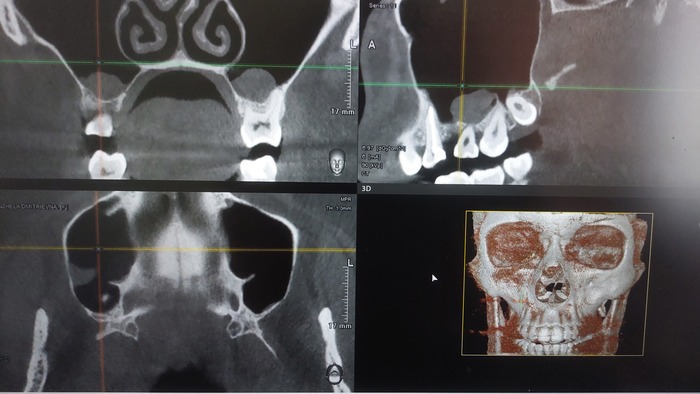

Я иду в клинику, там делают КТ челюсти, говорят что все оставшееся под удаление, процедура восстановления год, года у меня нет, я отказываюсь и ухожу. Слегка расстроена, конечно, но не жили красиво, не будем и начинать, в конце концов альтернатива у меня и так в наличии.

Приезжаю, кабинет у него в бизнес-центре на Обуховской обороны (СПБ), привожу запись кт... Он осматривает, ощупывает мои челюсти, смотреть КТ отказывается ("Это непоказательно, там бывают ложные затемнения, я делаю по необходимости отдельные снимки"), предлагает вариант верх 6 имплантов с немедленной нагрузкой, низ пролечивание пеньков+культевые вкладки+цирконовый мост+ 4 импланта и две конструкции из металоокерамики, там где пеньков нет. про свои ограниченич по срокам я тоже говорила, и сразу озвучила что если так нельзя, ок, я переживу, т.е не настаивала. да я в курсе про большую убыль кости, и это вопрос я задала одним из первых, на что получила ответ "отличная кость, ничего не надо наращивать"

Ну ок, он врач, он больше знает. При этом снимков челюсти за все время было сделано два или три, отдельных мест, где импланты вываливались (это важно, дальше поймете почему)

Врачи сейчас поймут с одного взгляда, не врачи -присмотритесь, где там та сама "отличная кость"? Один имплант держится буквально последним миллиметром.

И да, это та самая сторона которая все время доставляла мне беспокойство, и та где протез сломался.

Если честно, после всего описанного я совершенно не готова проходить этот путь с имплантацией второй раз. У меня снова сверху вставная челюсть, сделали мне ее очень хорошо и аккуратно и если честно мне намного легче с ней жить чем весь предыдущий год. Да, я почти уверена что так потому что протезирование верхней челюсти было сделано плохо. И, справедливости ради должна сказать что что-то таки было сделано хорошо, а именно мост на нижней челюсти. Хотя и там были оставлены недолеченные кисты (см снимок)